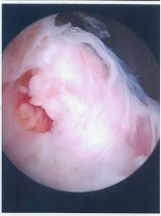

Η θεραπεία επιλογής είναι η αρθροσκόπηση του ώμου όπου μέσω 2-3 οπών του δέρματος εισάγουμε την αρθροσκοπική κάμερα και ειδικά σχεδιασμένα εργαλεία , αναγνωρίζουμε το σημείο βλάβης ( ρήξη του τένοντα) και διενεργείται η συρραφή και επανακαθήλωση της ρήξης του υπερακανθίου τένοντα στο μείζον βραχιόνιο όγκωμα. Ο ασθενής παραμένει για μία ημέρα στο νοσοκομείο και εξέρχεται με σταδιακό πρόγραμμα κινητοποίησης του ώμου.

Aρθροσκοπική επανακαθήλωση